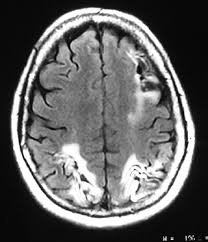

Posterior reversible encephalopathy syndrome PRES also known as reversible posterior leukoencephalopathy syndrome RPLS is a rare condition in which parts of the brain are affected by swelling usually as a result of an underlying causeSomeone with PRES may experience headache changes in vision and seizures with some developing other. 2015 require the use of ICD-10-CM codes.

Posterior reversible encephalopathy syndrome PRES also known as reversible posterior leukoencephalopathy syndrome RPLS is a rare condition in which parts of the brain are affected by swelling usually as a result of an underlying causeSomeone with PRES may experience headache changes in vision and seizures with some developing other.

Posterior reversible encephalopathy syndrome PRES also known as reversible posterior leukoencephalopathy syndrome RPLS is a rare condition in which parts of the brain are affected by swelling usually as a result of an underlying causeSomeone with PRES may experience headache changes in vision and seizures with some developing other. Reversible encephalopathy with cerebral vasospasm in a Guillain-Barré syndrome patient treated with intravenous immunoglobulin. I6784 Cerebral vasospasm and vasoconstriction. I67841 Reversible cerebrovascular vasoconstriction syndrome. 1 The true incidence of RCVS is not known. Reversible Cerebral Vasoconstriction Syndrome RCVS is a rare cause of thunderclap headache TCH estimated cause 8-45 of TCH once aneurysmal subarachnoid hemorrhage SAH is ruled out. I6784 Cerebral vasospasm and vasoconstriction.